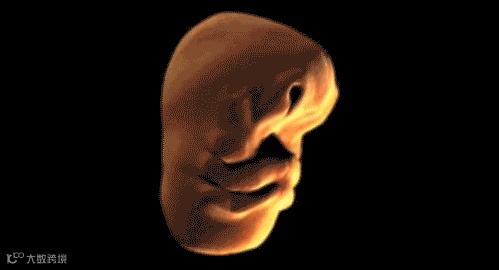

子宫内胎儿脸部发育过程——我们每个人都曾经很"丑"。